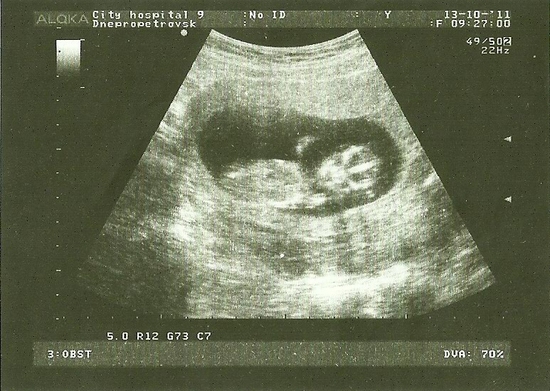

вот и сходила на УЗИ

Результаты: УЗИ, КТГ, доплера, скринингаувидела свою маську, такой прикольный малявчик, а вот собственно и мы

как мне кажется, улыбается. а вот результаты

спасибо, буду ждать похода в ЖК, а масика пока сфоткали... узистка сидела смеялась, говорит активный. кстати на работе удивились что так хорошо получился, я просто не знаю как должно быть, но все равно очень довольна первой фотографией.